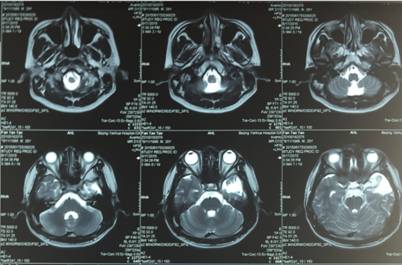

患者是一位28岁男性, 癫痫术后7年,2年前又频繁癫痫发作,于今年6月17日来我院神经外科门诊求治,门诊以“癫痫”收入院。患者常年规律口服抗癫痫药物,癫痫仍发作频繁,患者精神压力大。患者入院后,神经外科积极完善术前各项检查,应用长程视频脑电图监测捕捉癫痫发作波。经头颅增强MRI、头颅CT检查发现的致痫灶与视频脑电图监测出现癫痫波的部位吻合,明确了痫灶的部位。

6月21日,我院特邀北京天坛医院孙振荣教授、北大人民医院刘献增主任来院与我院专家共同对该患者进行了术前会诊评估及病例讨论。依据患者的症状、体征及入院检查结果,证实患者癫痫频繁发作,药物控制不佳,为左侧颞叶痫灶导致,病灶局限,适于手术治疗。

2015年06月23日上午在显微镜下行癫痫病灶切除术,术中持续皮层脑电监测。手术顺利完成。术后复查脑电图,患者脑电节律恢复正常,左侧颞叶癫痫波消失。目前患者恢复良好,未再癫痫发作。